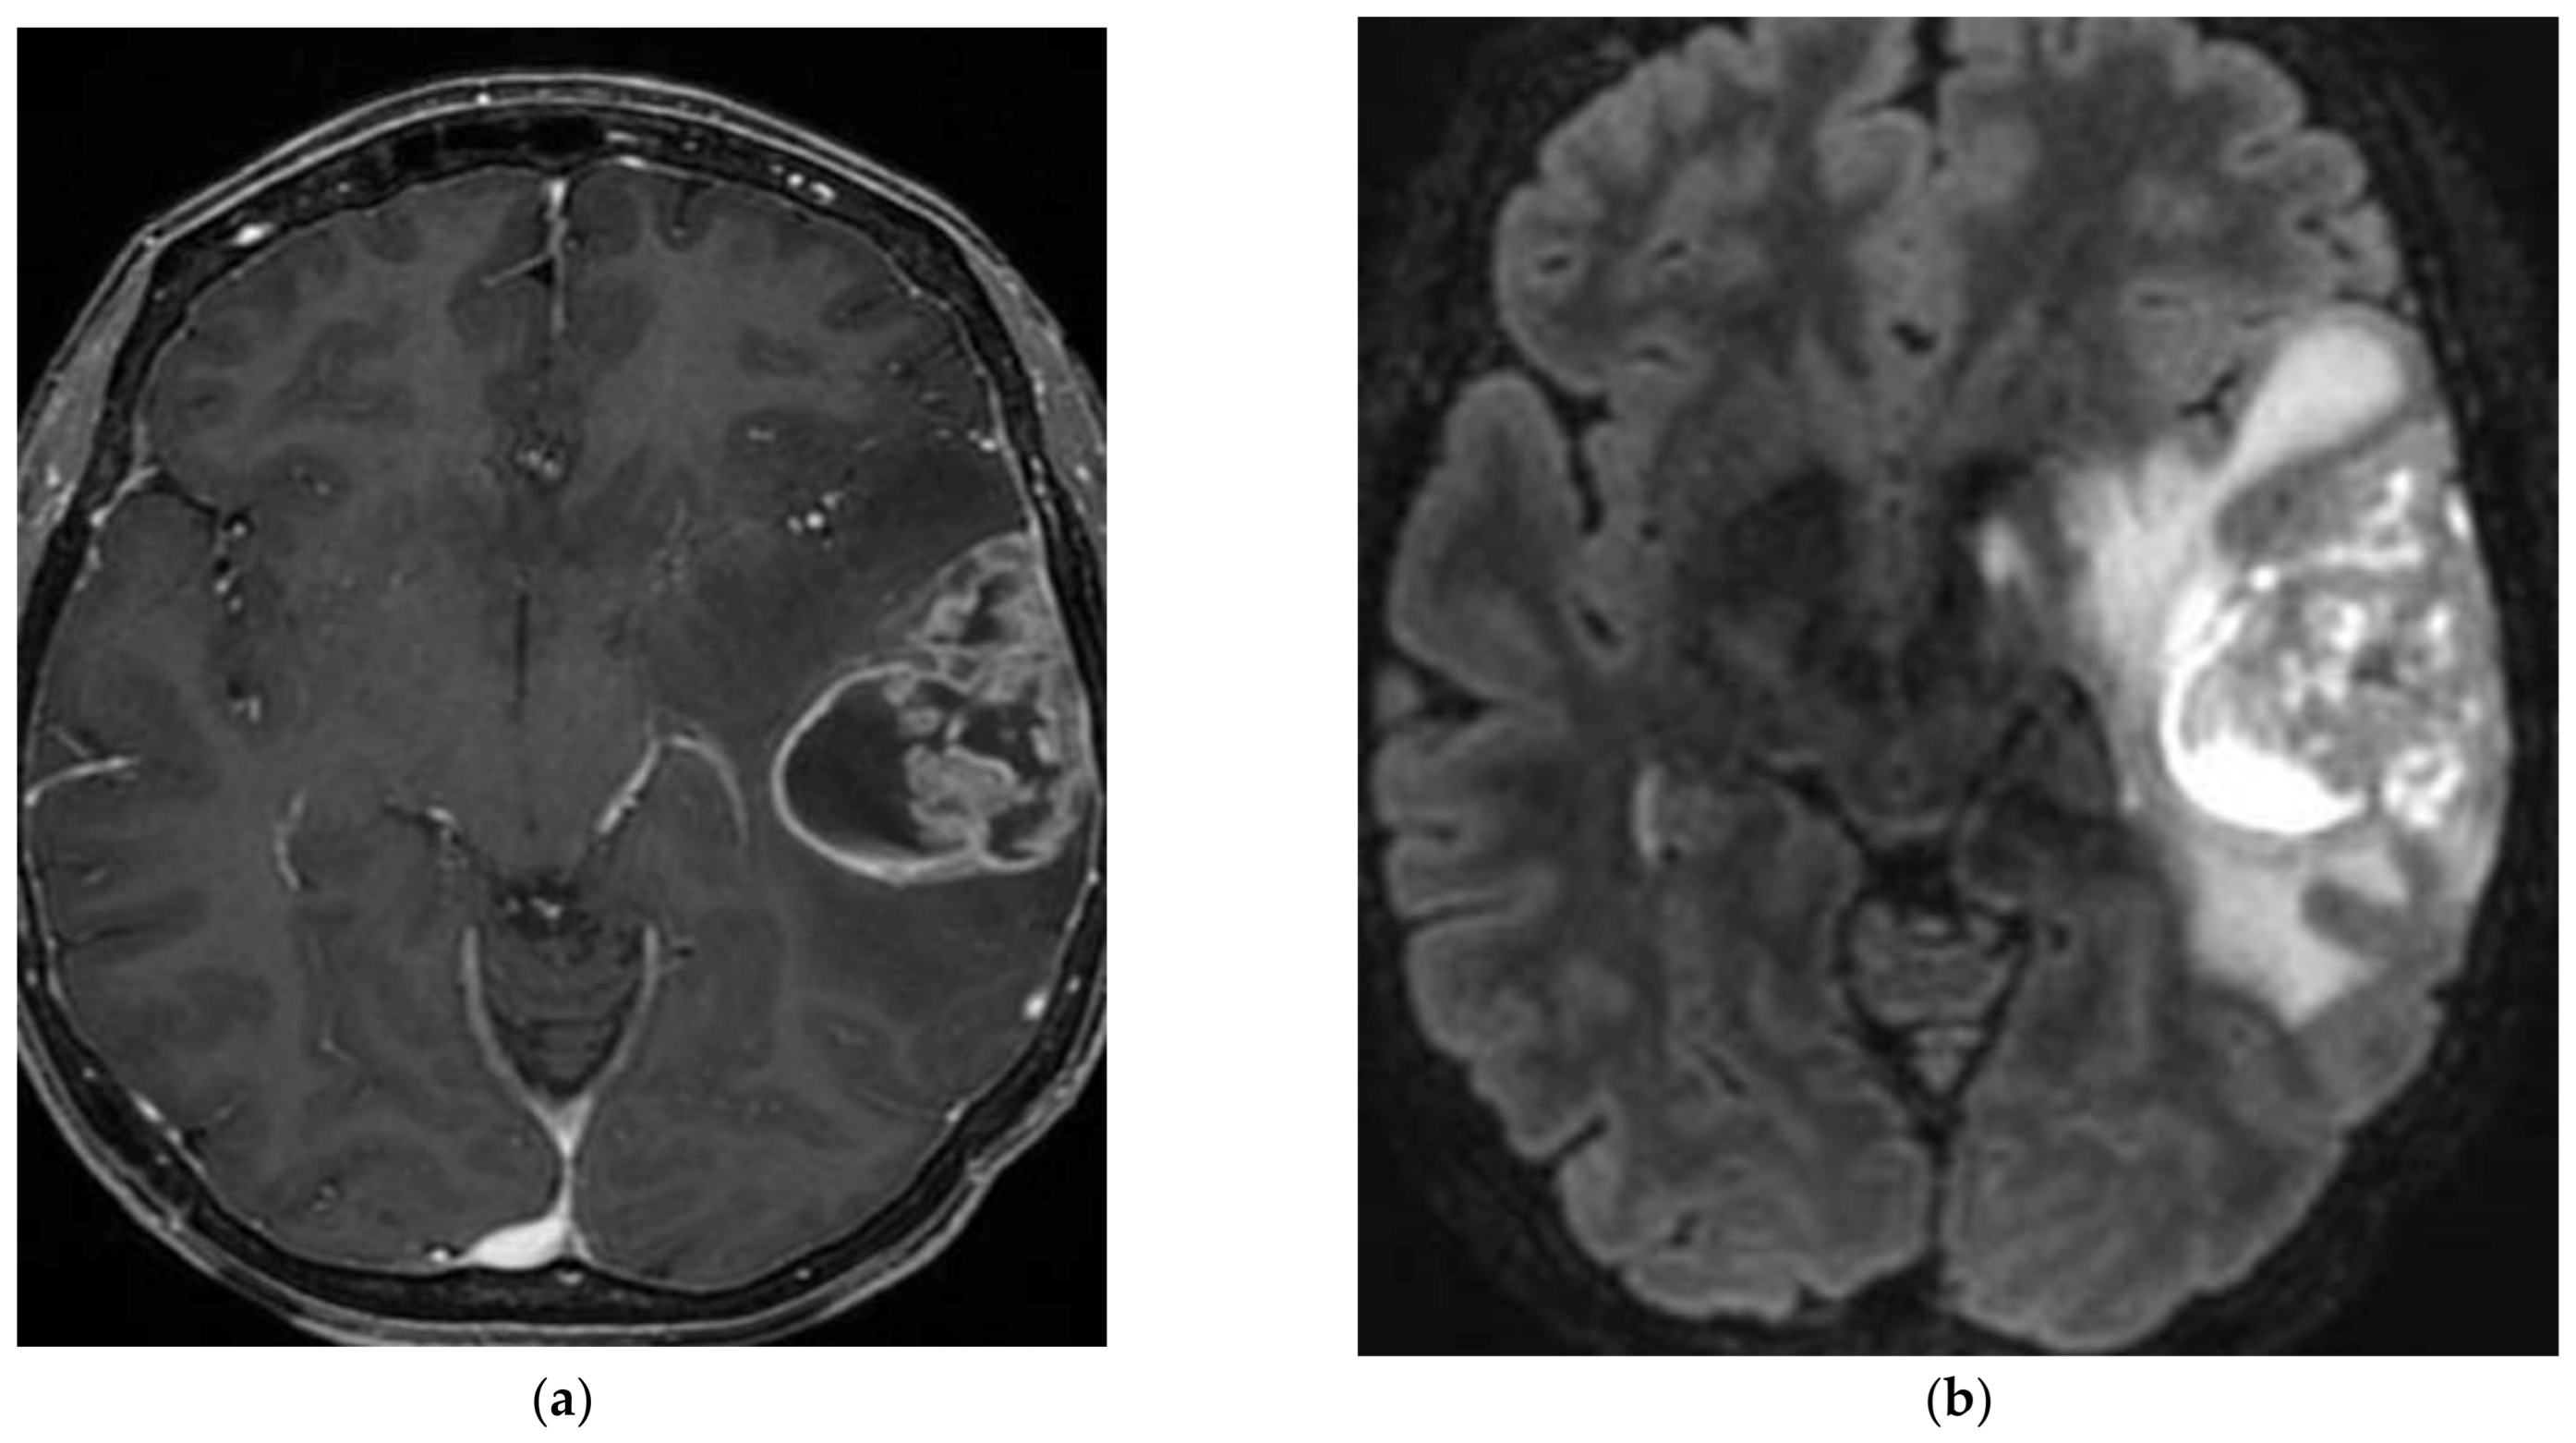

| Rosette-forming glioneuronal tumour (Figure 2) | 20 y | Midline structures in proximity of the 4th ventricle and the aqueduct of Sylvius | Neurocytes: Olig2+, rosettes: synaptophysin+, Glial cells: GFAP+, S100+ | FGFR1 mutations are very common, associated with PIK3CA, PIK3R1 or NF1 mutations [36] | Biphasic tumour with a component of neurocytes forming rosettes and/or pseudorosettes, and a glial component (often pilocytic astrocytes). | Progressive brainstem/cerebellar signs and visual disturbance. | Surgical resection is preferred [37]. If aggressive features and/or leptomeningeal infiltration, spinal metastasis: RT and chemotherapy [38] can be discussed in an adjuvant manner after surgery. Molecular targeted therapy*. | Mix of cystic and solid lesions, strong gadolinium enhancement. “Green bell pepper sign” [39]. |